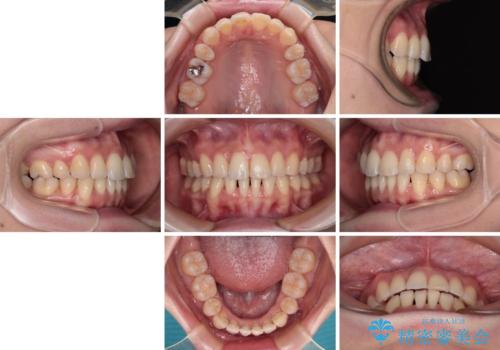

【モニター】飛び出した上顎前歯を抜歯矯正で引っ込める ワイヤー装置の抜歯矯正治療

- 口元の閉じにくさを気にして来院された患者様です。

上下ともに歯列が前方に突出していたため、上下左右の第一小臼歯4本を抜去し、ワイヤー装置による矯正治療を行うこととしました。

舌の突出癖による影響もあったため、舌のトレーニングを並行して実施しました。

舌の突出癖がなかなか改善されず、上下前歯の接触がやや甘い状態での仕上がりとなりました。

接触が甘い場合、上顎前歯の叢生が後戻りを起こしやすくなるため、治療終了後の保定期間でも舌のトレーニングを継続するように指示しています。